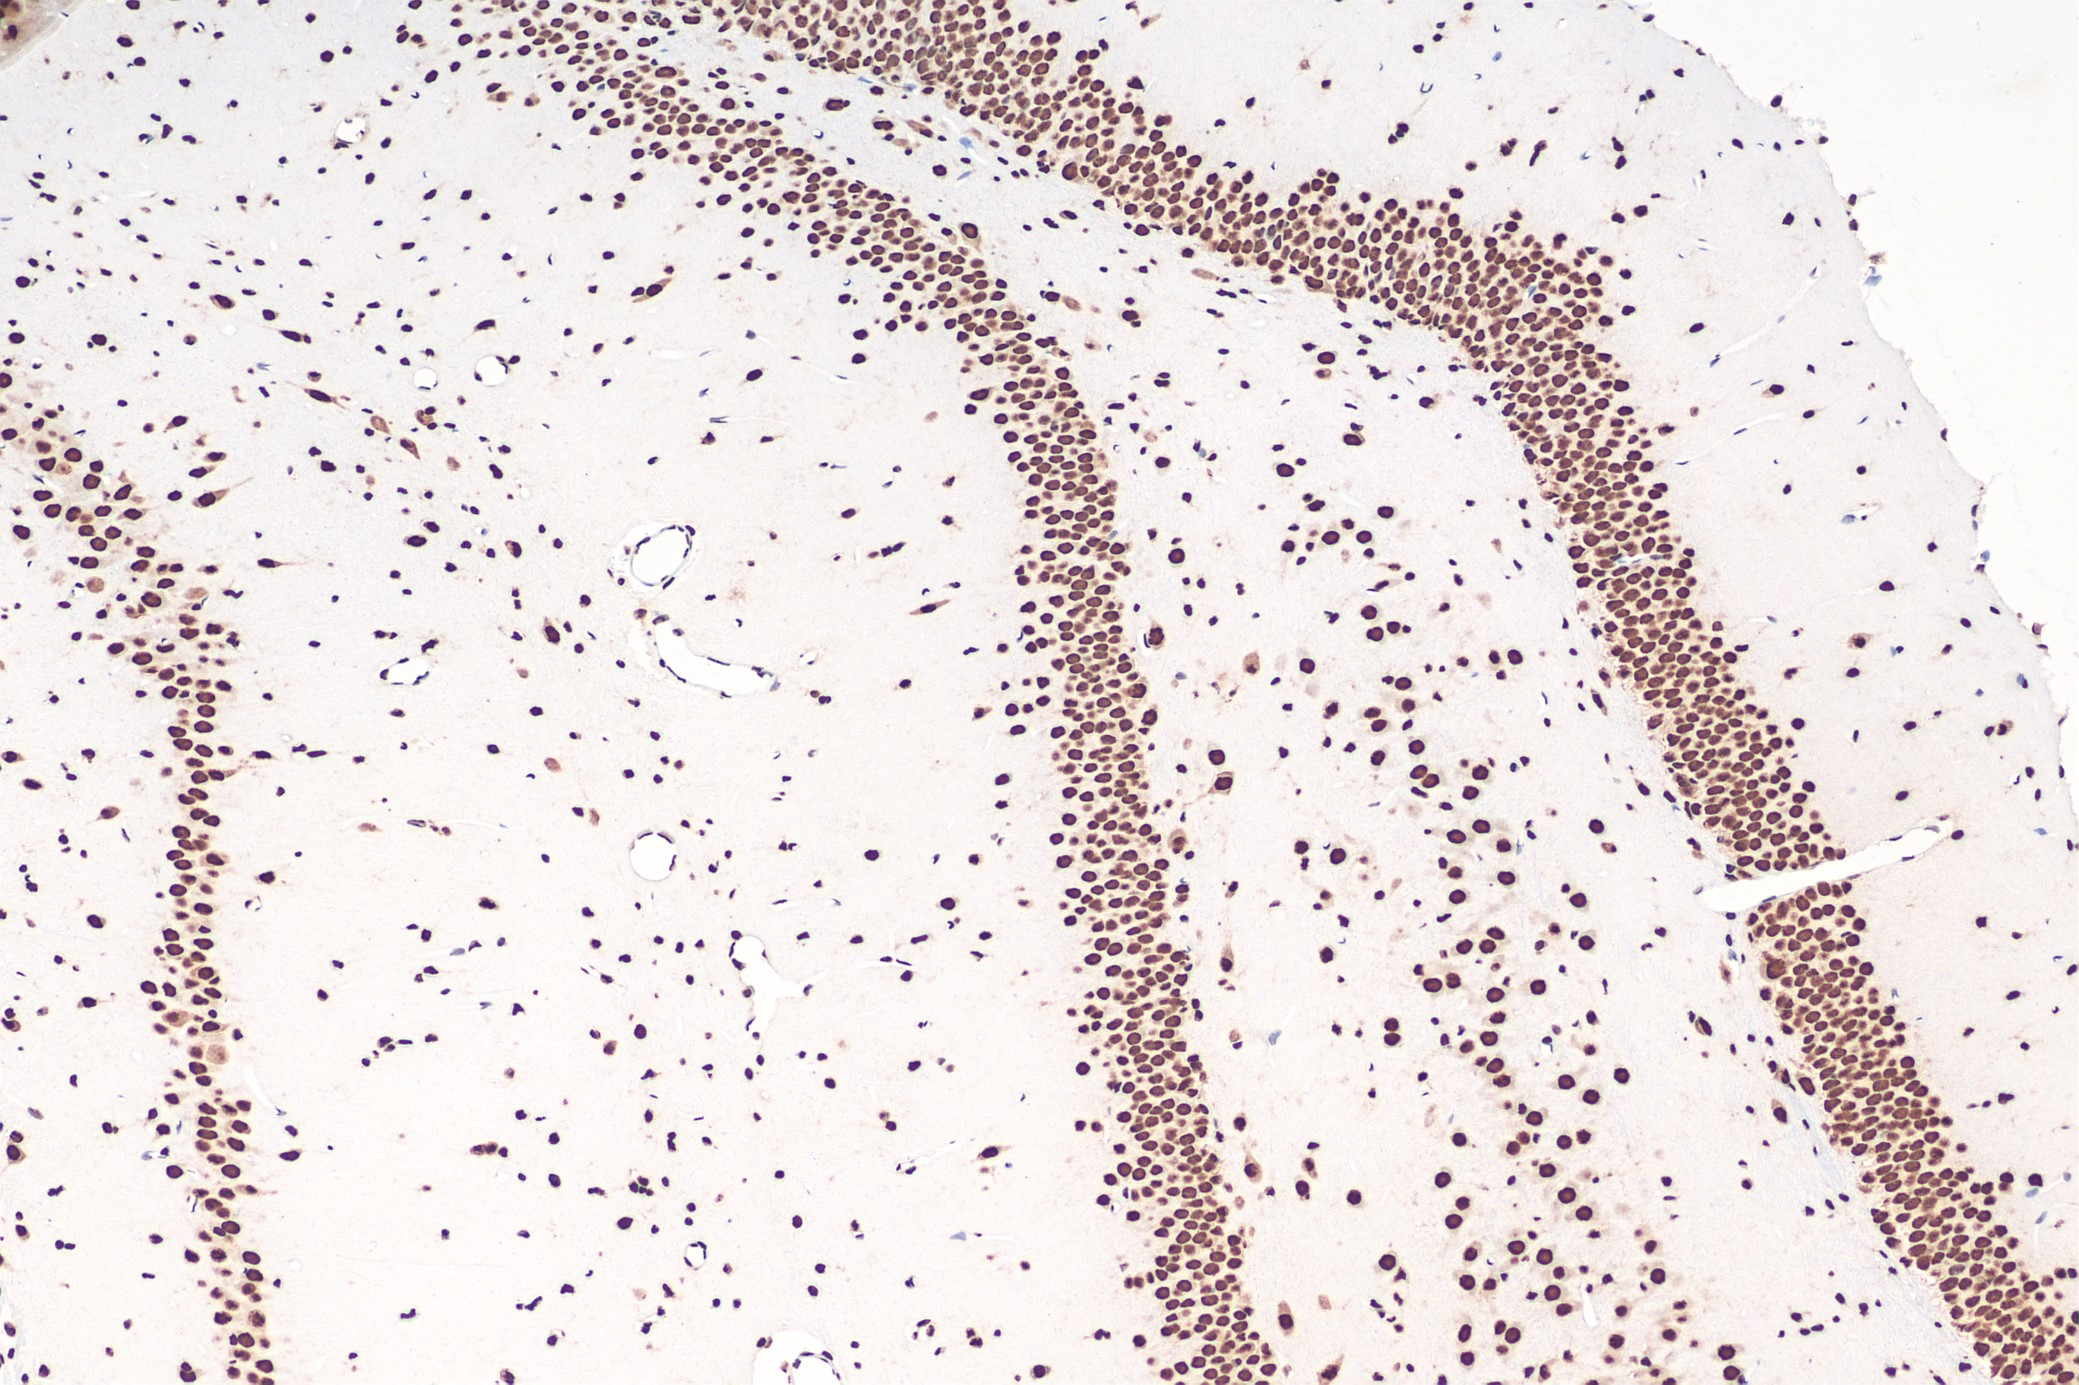

Immunohistochemical analysis of paraffin-embedded rat brain tissue slide using 80001-1-RR (TDP43 recombinant antibody) at dilution of 1:4000 (under 10x lens). Heat mediated antigen retrieval with Tris-EDTA buffer (pH 9.0). Multi-rAb™ Polymer HRP-Goat anti-Rabbit Recombinant secondary antibody RGAR011 was used for detection.

Immunohistochemical analysis of paraffin-embedded rat brain tissue slide using 80001-1-RR (TDP-43 antibody) at dilution of 1:4000 (under 10x lens). Heat mediated antigen retrieval with Tris-EDTA buffer (pH 9.0). Multi-rAb™ Polymer HRP-Goat anti-rabbit Recombinant secondary antibody RGAR011 was used for detection. The staining was performed on Celnovte's CNT360-M1 autostainer.

Immunohistochemical analysis of paraffin-embedded mouse brain tissue slide using 80001-1-RR (TDP-43 antibody) at dilution of 1:4000 (under 10x lens). Heat mediated antigen retrieval with Tris-EDTA buffer (pH 9.0). Multi-rAb™ Polymer HRP-Goat anti-rabbit Recombinant secondary antibody RGAR011 was used for detection. The staining was performed on Celnovte's CNT360-M1 autostainer.